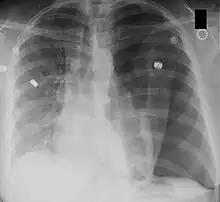

Left tension pneumothorax seen as a large, well-demarcated area devoid of lung markings with tracheal deviation and movement of the heart away from the affected side (mediastinal shift). There is also small pleural effusion on the left side.

Mediastinal shift is the deviation of the mediastinal structures towards one side of the chest cavity, usually seen on chest radiograph. It indicates a severe asymmetry of intrathoracic pressures.[1] Mediastinal shift may be caused by volume expansion on one side of the thorax, volume loss on one side of the thorax, mediastinal masses and vertebral or chest wall abnormalities. An emergent condition classically presenting with mediastinal shift is tension pneumothorax. It is also a useful indicator of malignant pleural effusion.[2]